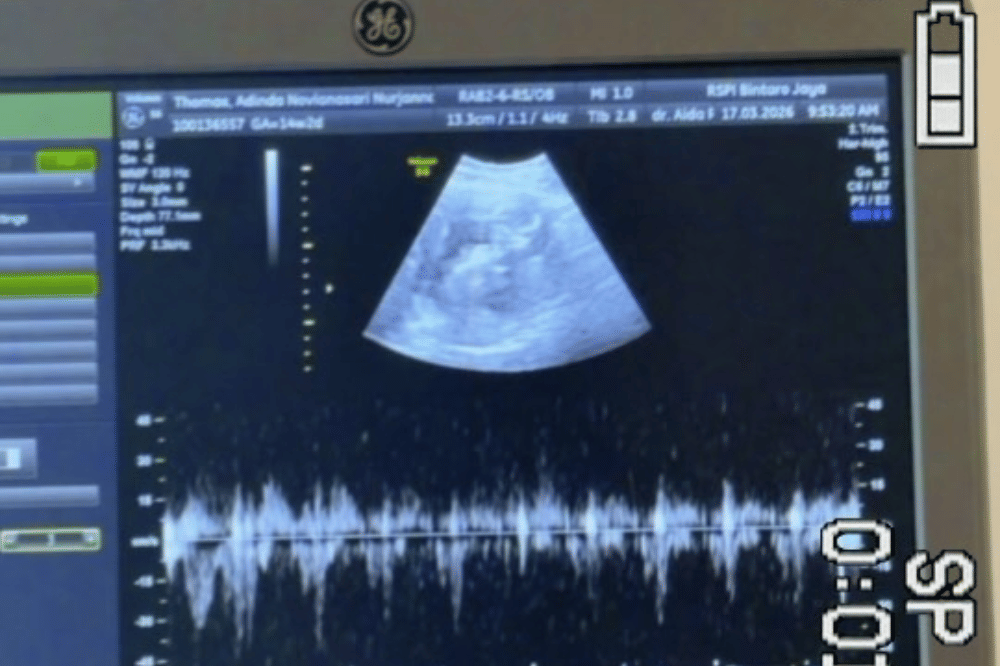

2. Berpose sambil menunjukkan hasil USG calon bayi

Dalam unggahannya, Adinda membagikan momen manis saat berpose dengan sang suami di photobooth.

Salah satu foto menampilkan keduanya tampak bahagia sambil menunjukkan hasil USG calon buah hati. Selain itu, Adinda juga terlihat memperlihatkan baby bump-nya yang semakin membesar.

5. Usia kehamilan Adinda sudah memasuki trimester kedua

Dalam unggahannya, Adinda juga membagikan video singkat saat melakukan pemeriksaan USG calon buah hatinya. Per 17 Maret 2026, usia kehamilan Adinda tercatat sudah memasuki 14 minggu atau sekitar 4 bulan.

Berdasarkan informasi ini, Adinda dan Raka diperkirakan akan menyambut kelahiran anak pertama mereka pada Agustus 2026 mendatang.